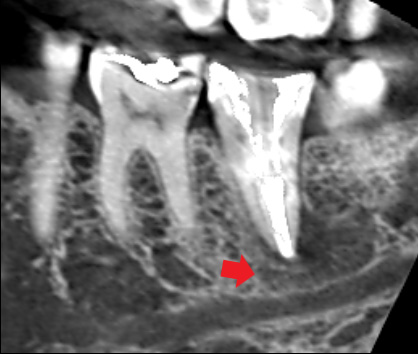

初診時のCT画像では、根の先に大きな膿の影がみられました。

下顎管という下あごの中に通っている太い神経達するほど大きい膿です。再根管治療を行い、根管の中の感染を徹底的に除去しました。